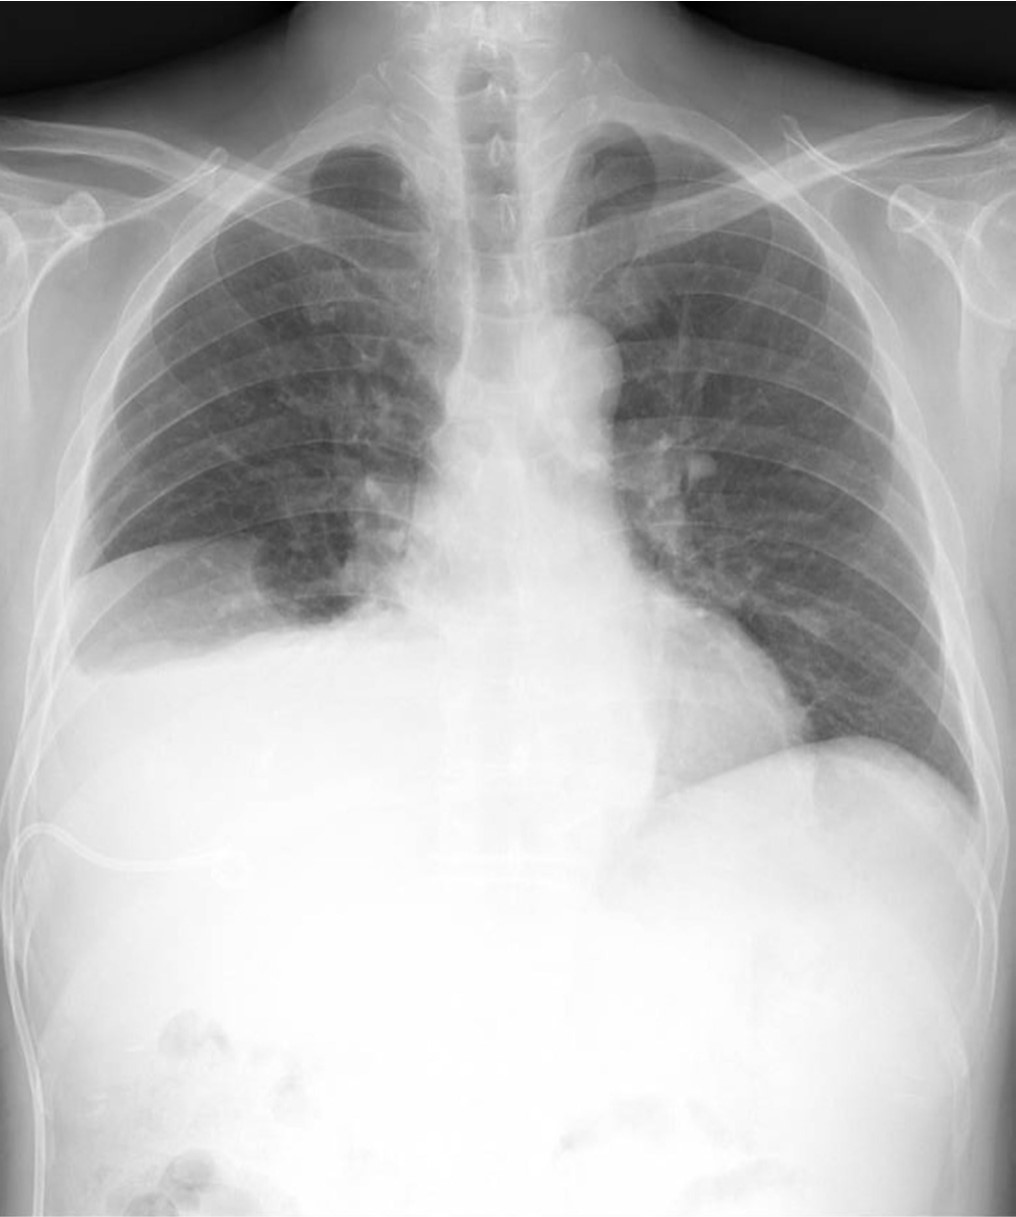

Fig. 2.

Fig. 2. Abdominal CT scan shows Rt. pleural effusion and right lower lobe consolidation.